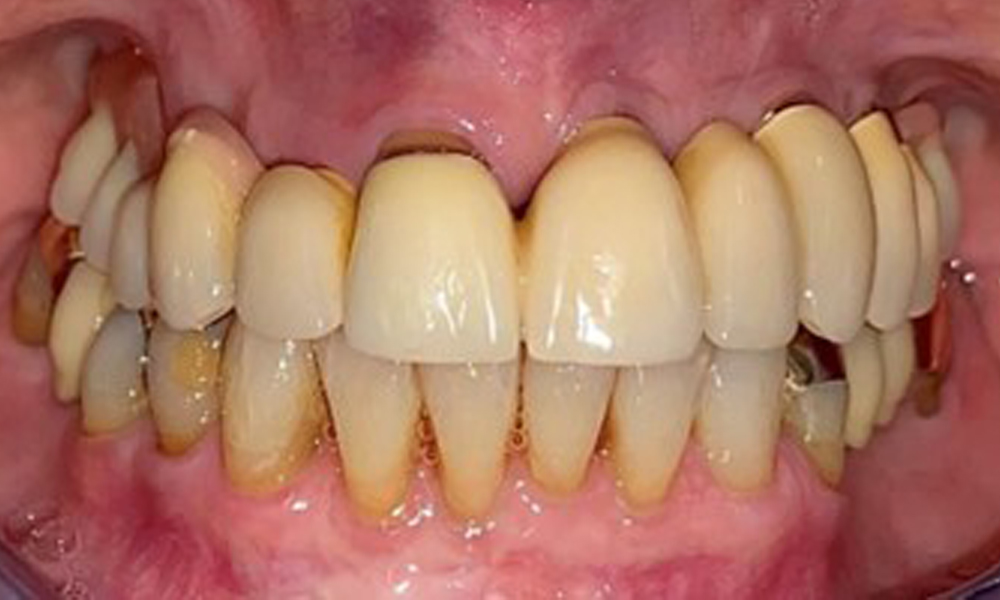

Die Patientin wurde vor über 25 Jahren mit einer kombinierten herausnehmbare Implantat-Teleskopprothese im Oberkiefer versorgt (Abb. 1, Abb. 2, Abb. 3) und ist sehr glücklich über ihren Zahnersatz. Im Unterkiefer hat die Patientin einen suffizienten festsitzenden Zahnersatz. (Abb. 4)

Dentaler Befund

Der dentale Befund stellt sich wie folgt dar: Kombinierte herausnehmbare Implantat- und zahngetragene Teleskoparbeit auf Implantaten 15, 13, 21, 23, 24, 25 und Zahn 11 (Abb. 1, Abb. 2, Abb. 3). Im Unterkiefer ist die Patientin mit einem festsitzenden Zahnersatz versorgt. 37–34 sowie 45–47 haben suffiziente Brücken (Abb. 4). Kronenränder sind intakt, aktive kariöse Läsionen sind nicht vorhanden. An Zahn 43 zeigt sich eine Compositefüllung mit Randspalt. Im Unterkiefer liegen Rezessionen mit freiliegender Wurzeloberfläche zwischen 1 – 3 mm vor. Dies trifft auch für 11 zu.